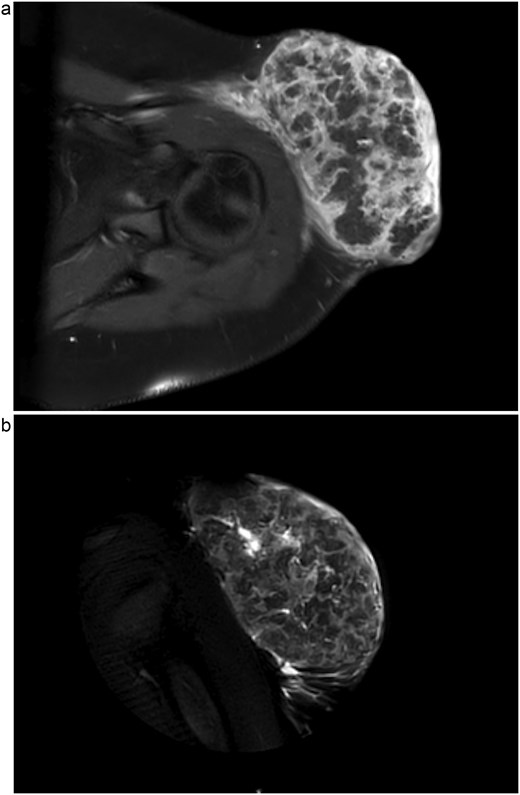

Upon admission, computed tomography (CT) and magnetic resonance imaging (MRI) revealed a 10.8 × 6.7 × 7.4 cm soft tissue mass overlying the left anterior shoulder and axillary lymphadenopathy. The MRI noted lack of a soft tissue plane between the mass and deltoid muscle, indicating possible invasion of the muscle tissue (Fig. 2a and b). The radiologist expressed concern for malignancy. Core needle biopsy of the mass described it as a cystic, partially solid mass comprised of necrotic ghost cells, multinucleated giant cells, basaloid epithelium, and squamous epithelium. These findings, accompanied by the tumour’s size, were sufficient for a diagnosis of giant pilomatricoma (Figs 3 and 4). A concurrent axillary lymph node biopsy was negative for lymphoproliferative disorder and malignancy. The PTHrP level was considerably elevated at 61.0 pmol/L (reference range 0–3.4 pmol/L). We suspected the pilomatricoma was secreting PTHrP and causing her hypercalcemia, a rare but documented occurrence in the literature [3].

1.5 Tesla MRI with axial view (a) and coronal view (b) showing a 10.8 × 6.7 × 7.4 cm left anterolateral shoulder soft tissue mass. This is suspicious for malignancy, most likely sarcoma, due to lack of a soft tissue plane between the tumour and the deep deltoid musculature as well as enlarged axillary lymph nodes (not shown).